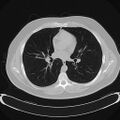

تصوير مقطعي محوسب للصدر (نافذة الرئة المحورية).